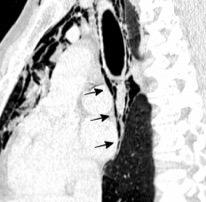

Traqueobroncomegalia de Mounier-Kuhn

Dilatación marcada de tráquea y grandes bronquios.

Traqueobroncomalacia 67% + Protrusión del tejido músculo-membranoso redundante entre los anillos cartilaginosos.(diverticulosis traqueal)

Infección respiratoria recurrente (88%)

Debilidad del aparato muco -ciliar Fumadores.